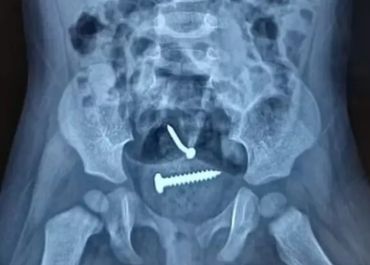

Pai é solto após laudo médico constar que bebê de 1 ano engoliu parafuso e não foi violentada em Pedro II (PI)

Homem é suspeito de violentar esposa e filha de 1 ano em Pedro II (PI); raio-X revela presença de objetos estranhos na criança